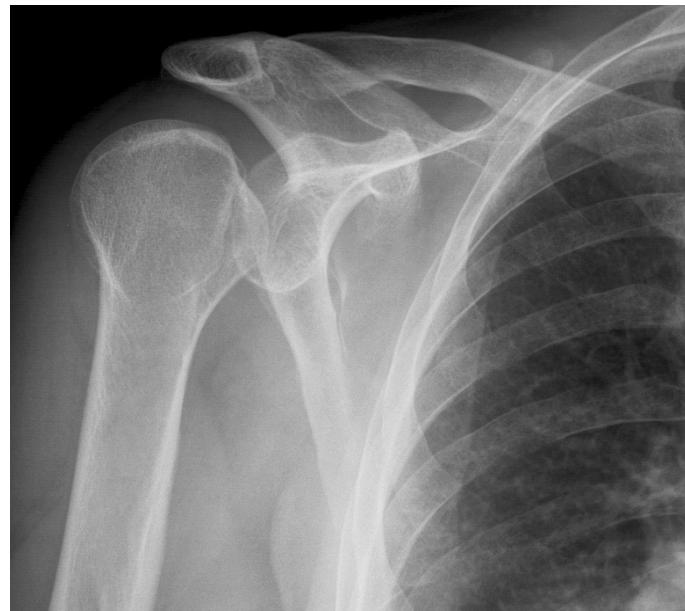

Clinical Scenario: 45 years old male fell from height and landed on his shoulder and presented to your clinic with painful shoulder.

Q17: What is the following test name and what does it test?

Apprehension test for anterior shoulder instability